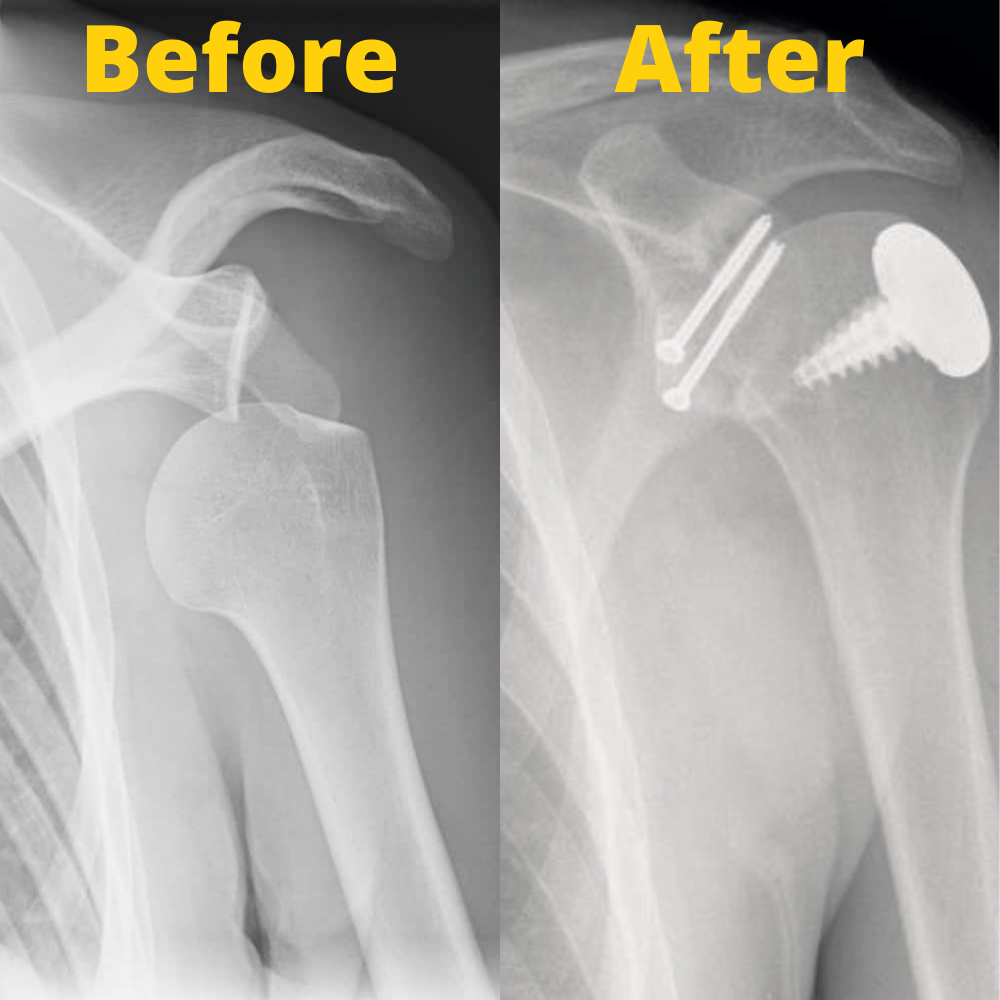

What Is Shoulder Bankart Repair . Minimally invasive surgical procedure to repair a tear of the glenoid labrum in the shoulder. This is a bankart lesion. A bankart repair procedure is sometimes necessary to treat shoulder instability. When your shoulder bone is forced out of its socket and into the glenoid labrum, it can tear it or even separate it from the bone. The bankart repair procedure, named after british surgeon arthur bankart, is a surgical technique that fixes recurrent shoulder dislocations by reattaching lax ligaments to. The labral tear surgery aims to repair and tighten overstretched and damaged. A bankart lesion repair is usually carried out arthroscopically (hey hole surgery) under general anaesthetic. Typically, it is indicated when a bankart lesion exists and the injury is in a. A bankart repair is a surgical procedure to prevent recurring anterior shoulder dislocations due to.

A bankart repair is a surgical procedure to prevent recurring anterior shoulder dislocations due to. A bankart repair procedure is sometimes necessary to treat shoulder instability. Typically, it is indicated when a bankart lesion exists and the injury is in a. The bankart repair procedure, named after british surgeon arthur bankart, is a surgical technique that fixes recurrent shoulder dislocations by reattaching lax ligaments to. Minimally invasive surgical procedure to repair a tear of the glenoid labrum in the shoulder. This is a bankart lesion. When your shoulder bone is forced out of its socket and into the glenoid labrum, it can tear it or even separate it from the bone. The labral tear surgery aims to repair and tighten overstretched and damaged. A bankart lesion repair is usually carried out arthroscopically (hey hole surgery) under general anaesthetic.

What Is Shoulder Bankart Repair When your shoulder bone is forced out of its socket and into the glenoid labrum, it can tear it or even separate it from the bone. The bankart repair procedure, named after british surgeon arthur bankart, is a surgical technique that fixes recurrent shoulder dislocations by reattaching lax ligaments to. This is a bankart lesion. A bankart repair procedure is sometimes necessary to treat shoulder instability. Typically, it is indicated when a bankart lesion exists and the injury is in a. The labral tear surgery aims to repair and tighten overstretched and damaged. A bankart lesion repair is usually carried out arthroscopically (hey hole surgery) under general anaesthetic. A bankart repair is a surgical procedure to prevent recurring anterior shoulder dislocations due to. Minimally invasive surgical procedure to repair a tear of the glenoid labrum in the shoulder. When your shoulder bone is forced out of its socket and into the glenoid labrum, it can tear it or even separate it from the bone.